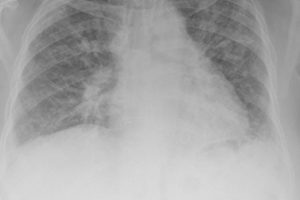

Real-world research on COPD

June Shannon spoke with Dr Sue Collier, Head of Medical Operations for the Salford Lung Study, about the latest results from this real-life COPD study published in the New England Journal of Medicine, and how its design promises to revolutionise future clinical trials

Exacerbators ‘must be identified’

Mortality rates are high among COPD patients who experience frequent acute exacerbations, Gary Culliton reports in his latest Clinical Update, where faster declines and poorer quality of life are also seen.